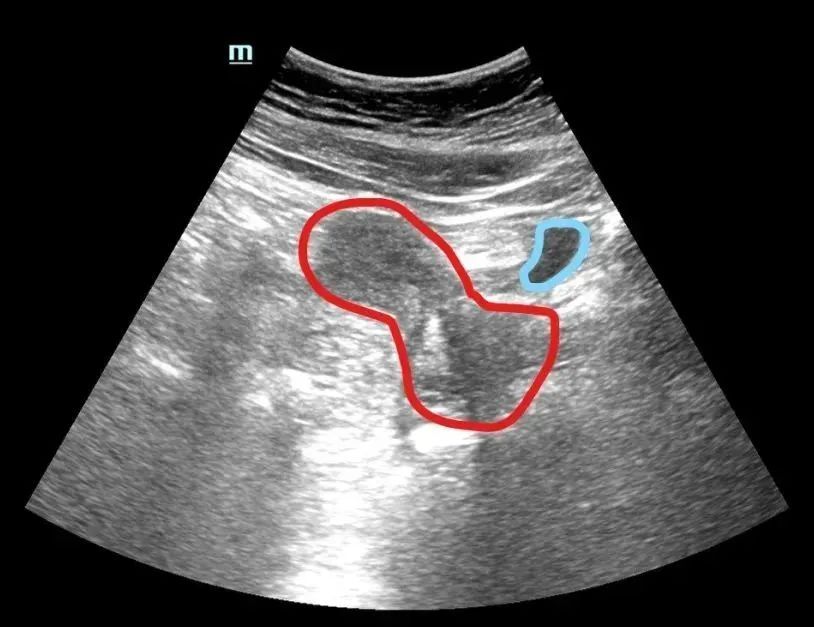

膀胱是一个空腔脏器,当无尿时它处于收缩状态,会阻挡超声探头发出的超声波。由于子宫、卵巢、前列腺等脏器均位于膀胱后下方盆腔较低、较深的位置,其前上方被大量肠管覆盖,超声波很难穿透肠道的气体到达这些脏器,无法看清是否有占位性病变。

而充满尿液的膀胱可有效地推开占据盆腔的肠管,还可以起到“打光”(专业上叫透声)的作用,减少肠道气体对需要检查脏器的干扰,使各种器官“照”出来的“照片”更清晰。